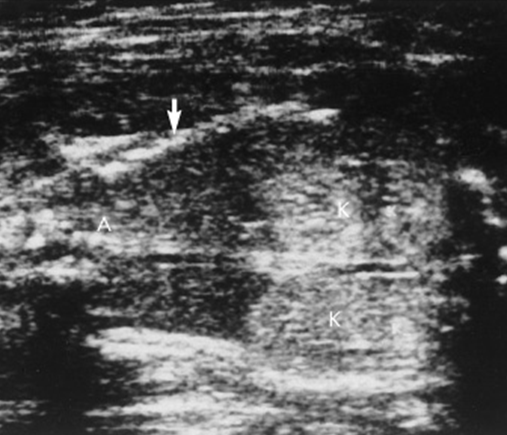

renal agenesis

Urachal cyst